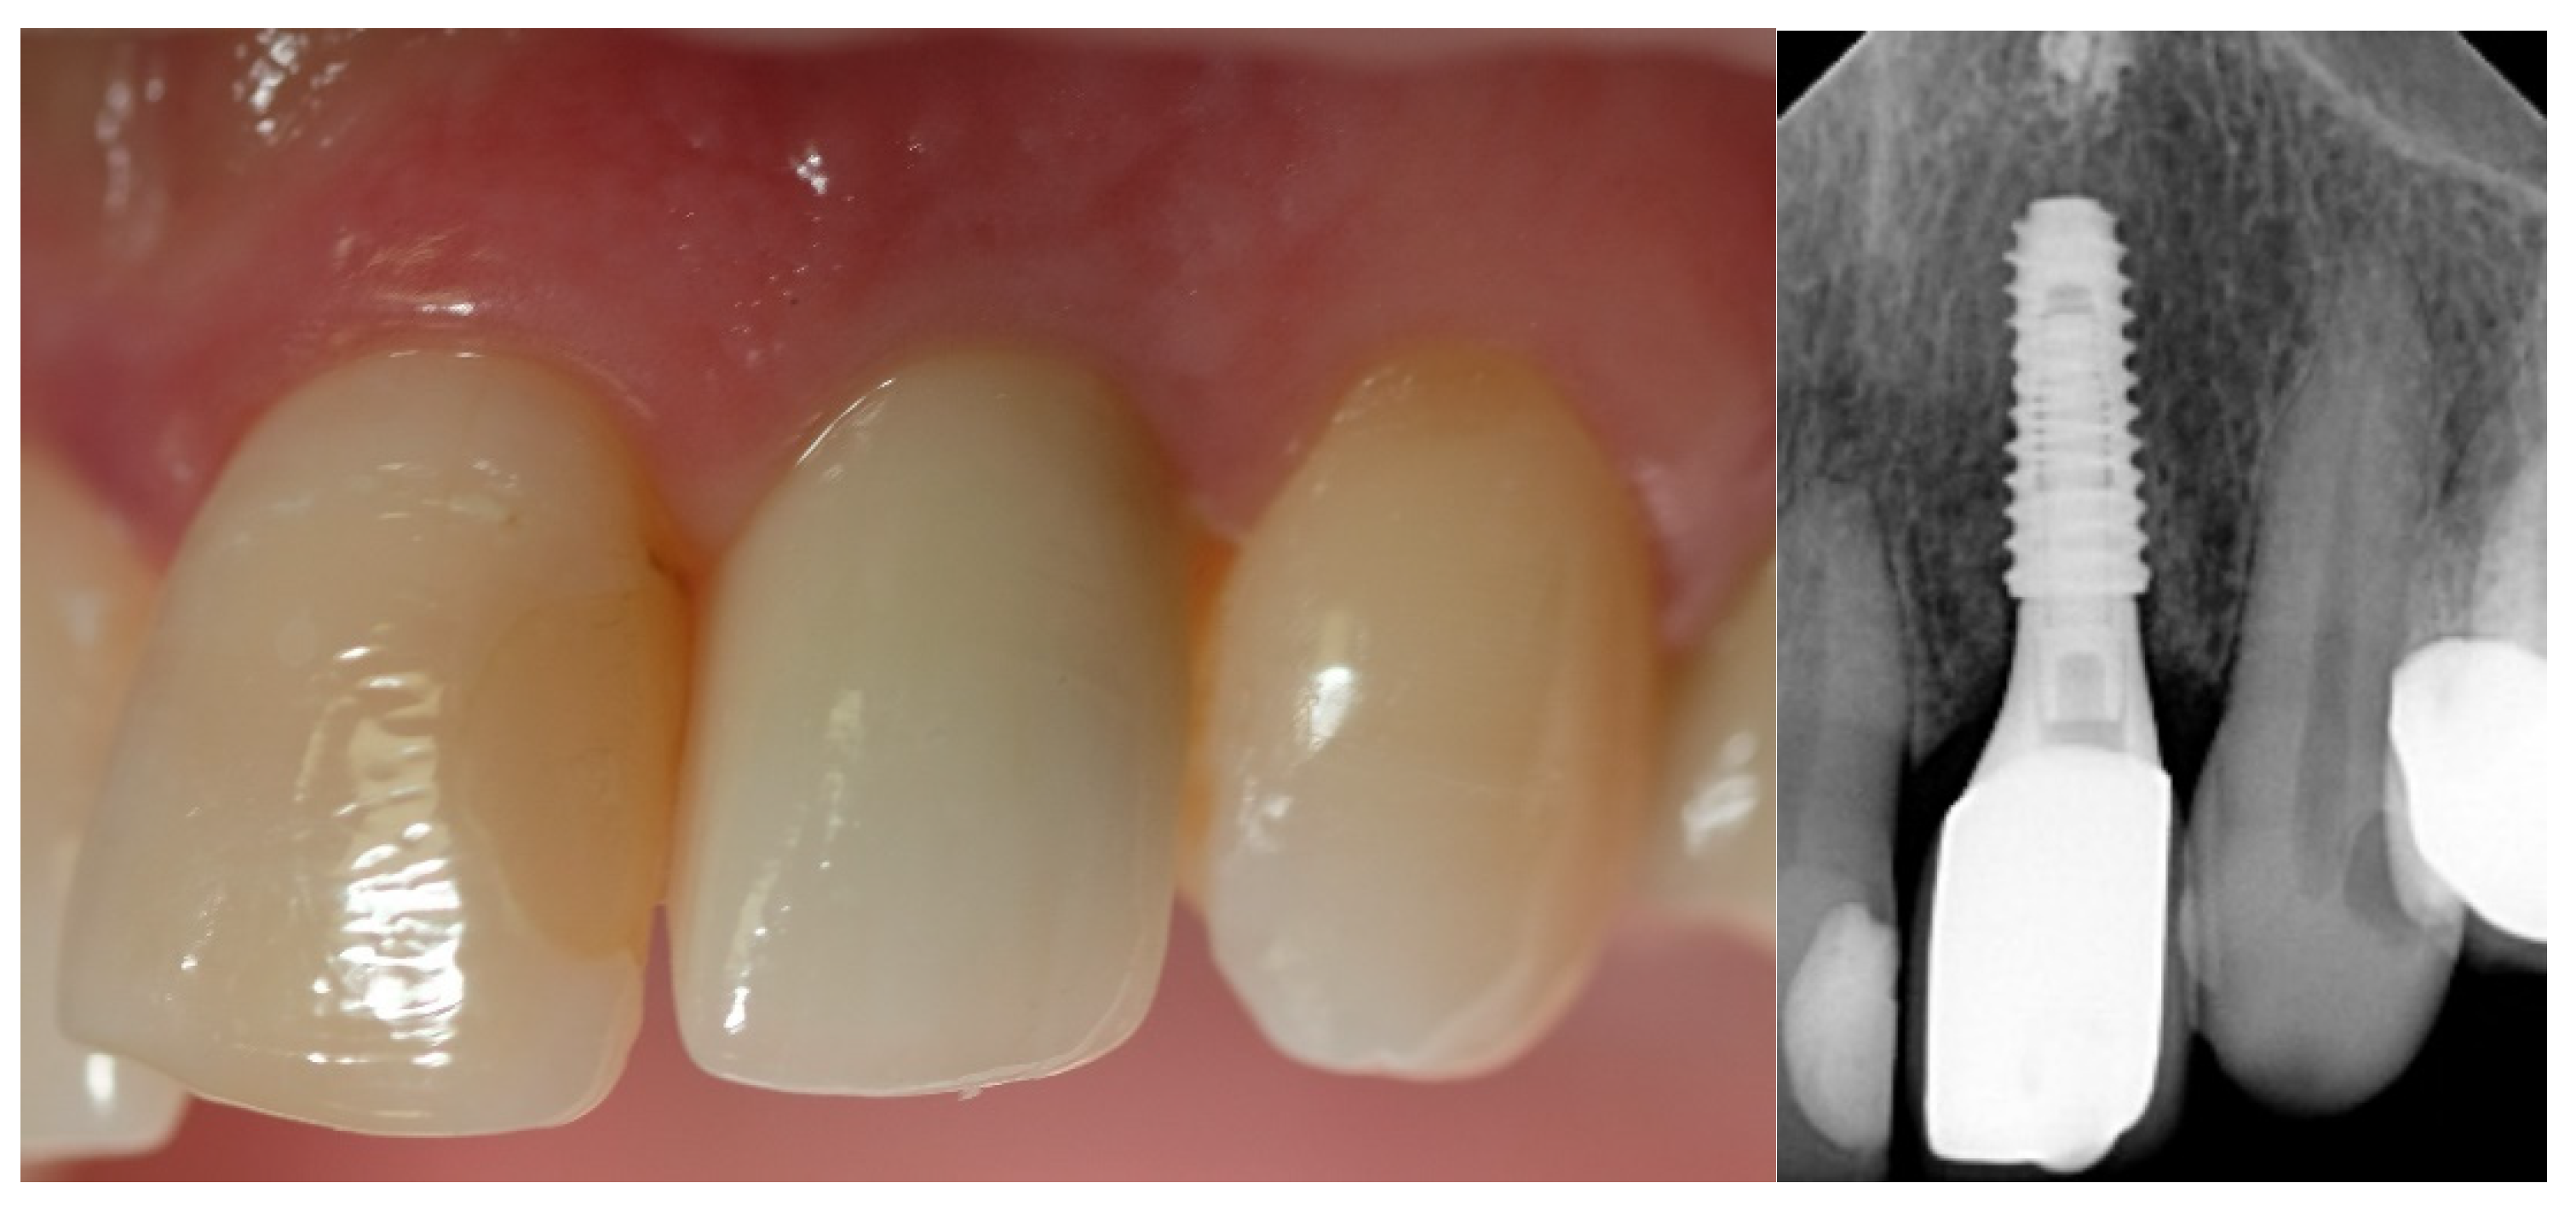

- Esthetic evaluation of clinical pictures, including at least two adjacent teeth, taken at two years after loading was done following the pink esthetic score (PES) proposed by Fürhauser et al., in 2005 [31]. In brief, the PES score evaluates seven variables: mesial papilla, distal papilla, soft tissue level, soft tissue contour, alveolar process deficiencies, soft tissue color and texture. A 0-1-2 scoring system was used, with a maximum achievable score of 14 per site.

| PES 3 at the 2-year follow-up | 12.6 ± 0.97 | 12.2 ± 0.92 | 0.3554 |

| MBL4 at the 2-year follow-up | 0.23 ± 0.11 | 0.18 ± 0.12 | 0.3339 |